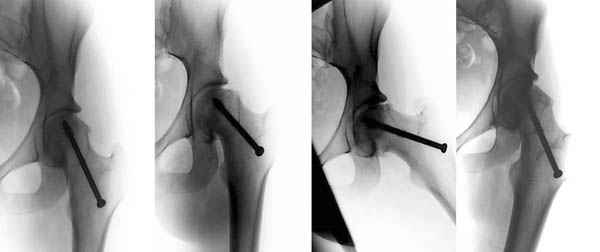

Позвольте представить Вашему вниманию вариант компоновки аппарата. Подробно методика закрытой декомпрессии тазобедренного сустава в сочетании с пролонгированной стимуляцией процессов остеогенеза описана в книге ШевцоваВ.И., Макушина В.Д. "Остеохондропатия тазобедренного сустава: Руководство для врачей". - М:ОАО "Издательство "Медицина", 2007.

Откуда и взят прилагаемый рисунок.

Уважаемый Ильдар Фуатович!

Юрий Алексеевич Булахтин